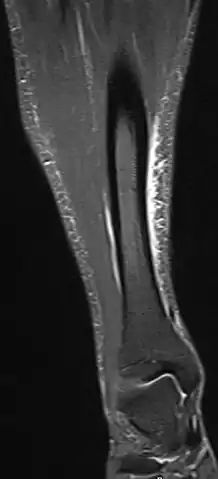

MRI of the left lower leg-severe “shin-splint”

Magnetic resonance image of the lower leg in the coronal plane showing high signal (bright) areas around the tibia as signs of shin splints.